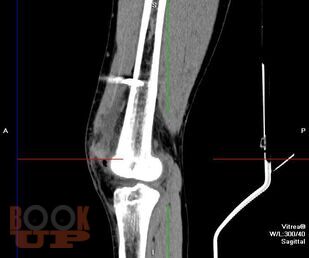

В учебно-методическом пособии представлены этиология, патогенез, клиника, осложнения, лечение, комплексная ультразвуковая, рентгенологическая, мультиспиральная компьютерная томографическая семиотика острого гематогенного остеомиелита у детей. Пособие раскрывает современные подходы ранней диагностики острого гематогенного остеомиелита у детей и предлагает оптимальный алгоритм ранней диагностики.